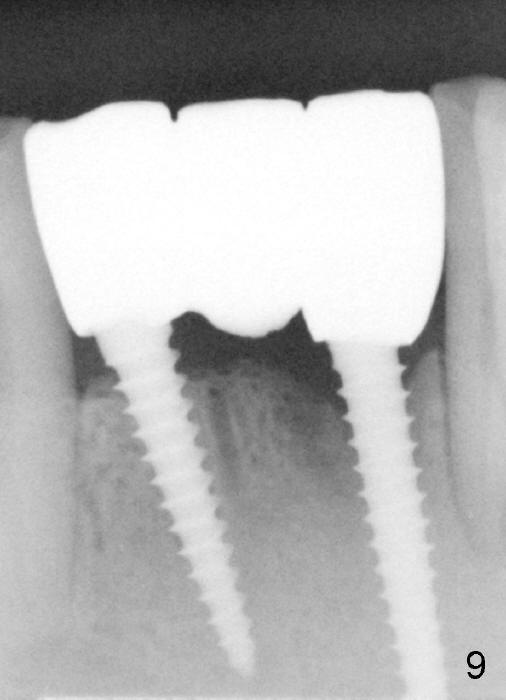

Fig.7 shows these two one piece implants immediately prior to cementation of the FPD (Fig.8). They are much more parallel to each other after prep, as compared to Fig.6. Fig.9 shows apparent bone growth around #24 implant (at the crest) 6,9 months post cementation and surgery, respectively. Orthodontic treatment will incorporate the fixed partial denture. Fig.10 shows that bone grows coronally (arrow) to cover 3 threads (from #6 thread to #3) at the site of #24 one year after functioning. There is mild buccal gingival infection involving #26 retainer. Preop CBCT is reviewed to determine whether it is related to potential thread exposure. It appears that at the sites of #24 (Fig.13,14) and 26 (Fig.11,12), 2.5 mm implant is more appropriate for the narrow ridge than 3.0 mm one. In fact, periimplantitis develops at #26 two years of absence of perio maintenance (because of atrial fibrillation with blood thinner; Fig.15, 3 years 7 months post cementation). Periimplantitis persists 4.5 months later. Although water pik is purchased, it is not used often because of low blowing force. If needed, remove the FPD atraumatically. Unwind the implant, clean the coronal threads with Titanium brush or remove the exposed threads and replant the implant with bone graft.